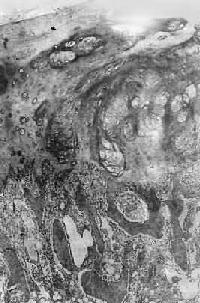

图17-5 骨巨细胞瘤 肿瘤位于肱骨上端,骨皮质破坏,有病理性骨折 镜下,肿瘤主要由单核基质细胞及多核巨细胞等两种细胞组成(图17-6),间质血管丰富。基质细胞为梭形、卵圆形或圆形,细胞境界不清楚,常见胞浆突起。细胞核较大,染色质量中等,可具有一个核仁。多核巨细胞常较均匀地散布在基质细胞之间,是为本瘤的特点。多核巨细胞的直径常为30~60μm,核数一般为15~20个,最多可达100个以上,常聚集在细胞的中央。核的形态与单核基质细胞相似。细胞边界不规则,但分界较清楚,胞浆丰富,略呈嗜碱性,有时还可见含大量脂类的泡沫细胞。本瘤间质血管丰富,有多少不等的胶原纤维。肿瘤本身无成骨现象,但有时见有类骨组织及新生骨小梁,常见于纤维组织的周围,可能是一种反应性新骨形成或病理性骨折后形成的骨痂。

图17-6 骨巨细胞瘤(Ⅰ级) 肿瘤由大量基质细胞和多核巨细胞两种细胞组成 【病理分级】 骨巨细胞瘤在病理组织学上,根据基质细胞和多核巨细胞的数量及异型性的程度分为三级:基质细胞分化好,形态大小一致,偶见核分裂像。多核巨细胞数量多、体积大、细胞核多者为Ⅰ级;基质细胞分化差,异型性明显,细胞密度高,核分裂像多,具有肉瘤样改变。多核巨细胞数量少、体积小、细胞核也少,有明显的异型性者为Ⅲ级;介于两者之间者为Ⅱ级。Ⅰ级基本为良性,具低度侵袭性,刮除术后可复发。多次复发后可变为恶性。Ⅲ级呈恶性肿瘤的表现,易复发和转移至肺。病理分级对判断骨巨细胞瘤的良恶性程度和预后以及治疗方法的选择有一定的参考价值,但并非绝对可靠。 【临床病理联系】 早期症状是局部疼痛及压痛,疼痛性质可为间歇性。位于浅表部位者,可出现局部肿胀或肿块。当肿瘤增大而使表面骨皮质膨胀变薄时,触之有捏乒乓球样感觉。位于脊椎的肿瘤,可引起相应神经压迫症状。 (四)骨肉瘤 骨肉瘤(osteosarcoma)是指肿瘤细胞能直接形成肿瘤性类骨组织或骨组织的恶性肿瘤。骨肉瘤是原发性骨恶性肿瘤中最常见者,约占骨恶性肿瘤的1/3。骨肉瘤的发病率在男性略高,可发生于各级年龄,但最多见于11~20岁,其次为21~30岁,年龄越大,发病率越低。骨肉瘤多发生在骨骼生长发育的旺盛时期,其恶性程度又较高,因此是严重影响劳动生产力并危及生命的重要肿瘤之一,早期诊断及早期治疗具有特别重要意义。 【病因】 骨肉瘤病因不明,其发生与下列因素有关。①骨骼的活跃生长。②放射线:实验证明凡能在骨骼内积存的放射性物质均可诱发骨肉瘤;某些骨疾患如骨巨细胞瘤、动脉瘤性骨囊肿或骨外肿瘤如乳腺瘤、视网膜母细胞瘤等的局部放射线照射治疗,偶尔可引起继发性骨肉瘤。③遗传:视网膜母细胞瘤基因(Rb基因,位于染色体13q14,目前已知它是一种抑癌基因)突变或缺失的遗传性视网膜母细胞瘤患者,发生骨肉瘤的危险性远远高于一般人。近年发现一些骨肉瘤患者也有Rb基因的突变。④病毒:实验证明,动物的骨肉瘤与病毒感染有关,但对人类骨肉瘤尚未有确切的材料说明与病毒的关系。⑤良性骨疾患的恶变:如多发性骨软骨瘤、骨Paget病、骨纤维结构不良等可恶变而发生骨肉瘤,亦称为继发性骨肉瘤。 【病理变化】 骨肉瘤可发生于任何骨,最常见于四肢长骨,半数以上发生于股骨的下端及胫骨或腓骨的上端,其次为肱骨上端。颌骨、脊椎骨、肩胛骨和髂骨等较少见。长骨的骨肉瘤发病年龄较小,发生于扁骨者年龄较大。大多数骨肉瘤发生于骨的内部或中央,在长骨位于干骺端,肿瘤在骨髓腔内及向周围骨皮质浸润形成肿块。因骨骺软骨对骨肉瘤的浸润具有一定的抵抗力,在骨骺板闭合骨化之前(约17~20岁),一般不侵及骨骺端。少数骨肉瘤发生于骨表面,称为皮质旁骨肉瘤,其临床、X线和病理表现均与一般骨肉瘤不同。 肉眼观,长骨肿瘤位于干骺端的骨髓腔中央或为偏心性。一侧或四周的骨皮质被浸润和破坏,其表面的骨外膜常被掀起。在切面上可见肿瘤上、下两端的骨皮质和掀起的骨外膜之间形成三角形隆起,其间堆积由骨外膜产生的新生骨。此三角称为Codman三角,这在X线照片中可以显示出来。在骨外膜被掀起时,自骨外膜通往骨皮质的小血管因受到牵拉而呈垂直于骨皮质分布,在这些垂直的小血管周围,组织的血液供应丰富,故新骨形成增多,这些反应性新生骨小梁呈放射状与骨表面垂直分布(图17-7),在X线上表现为日光放射状阴影,这种现象与上述Codman三角在X线上对骨肉瘤的诊断具有特征性。